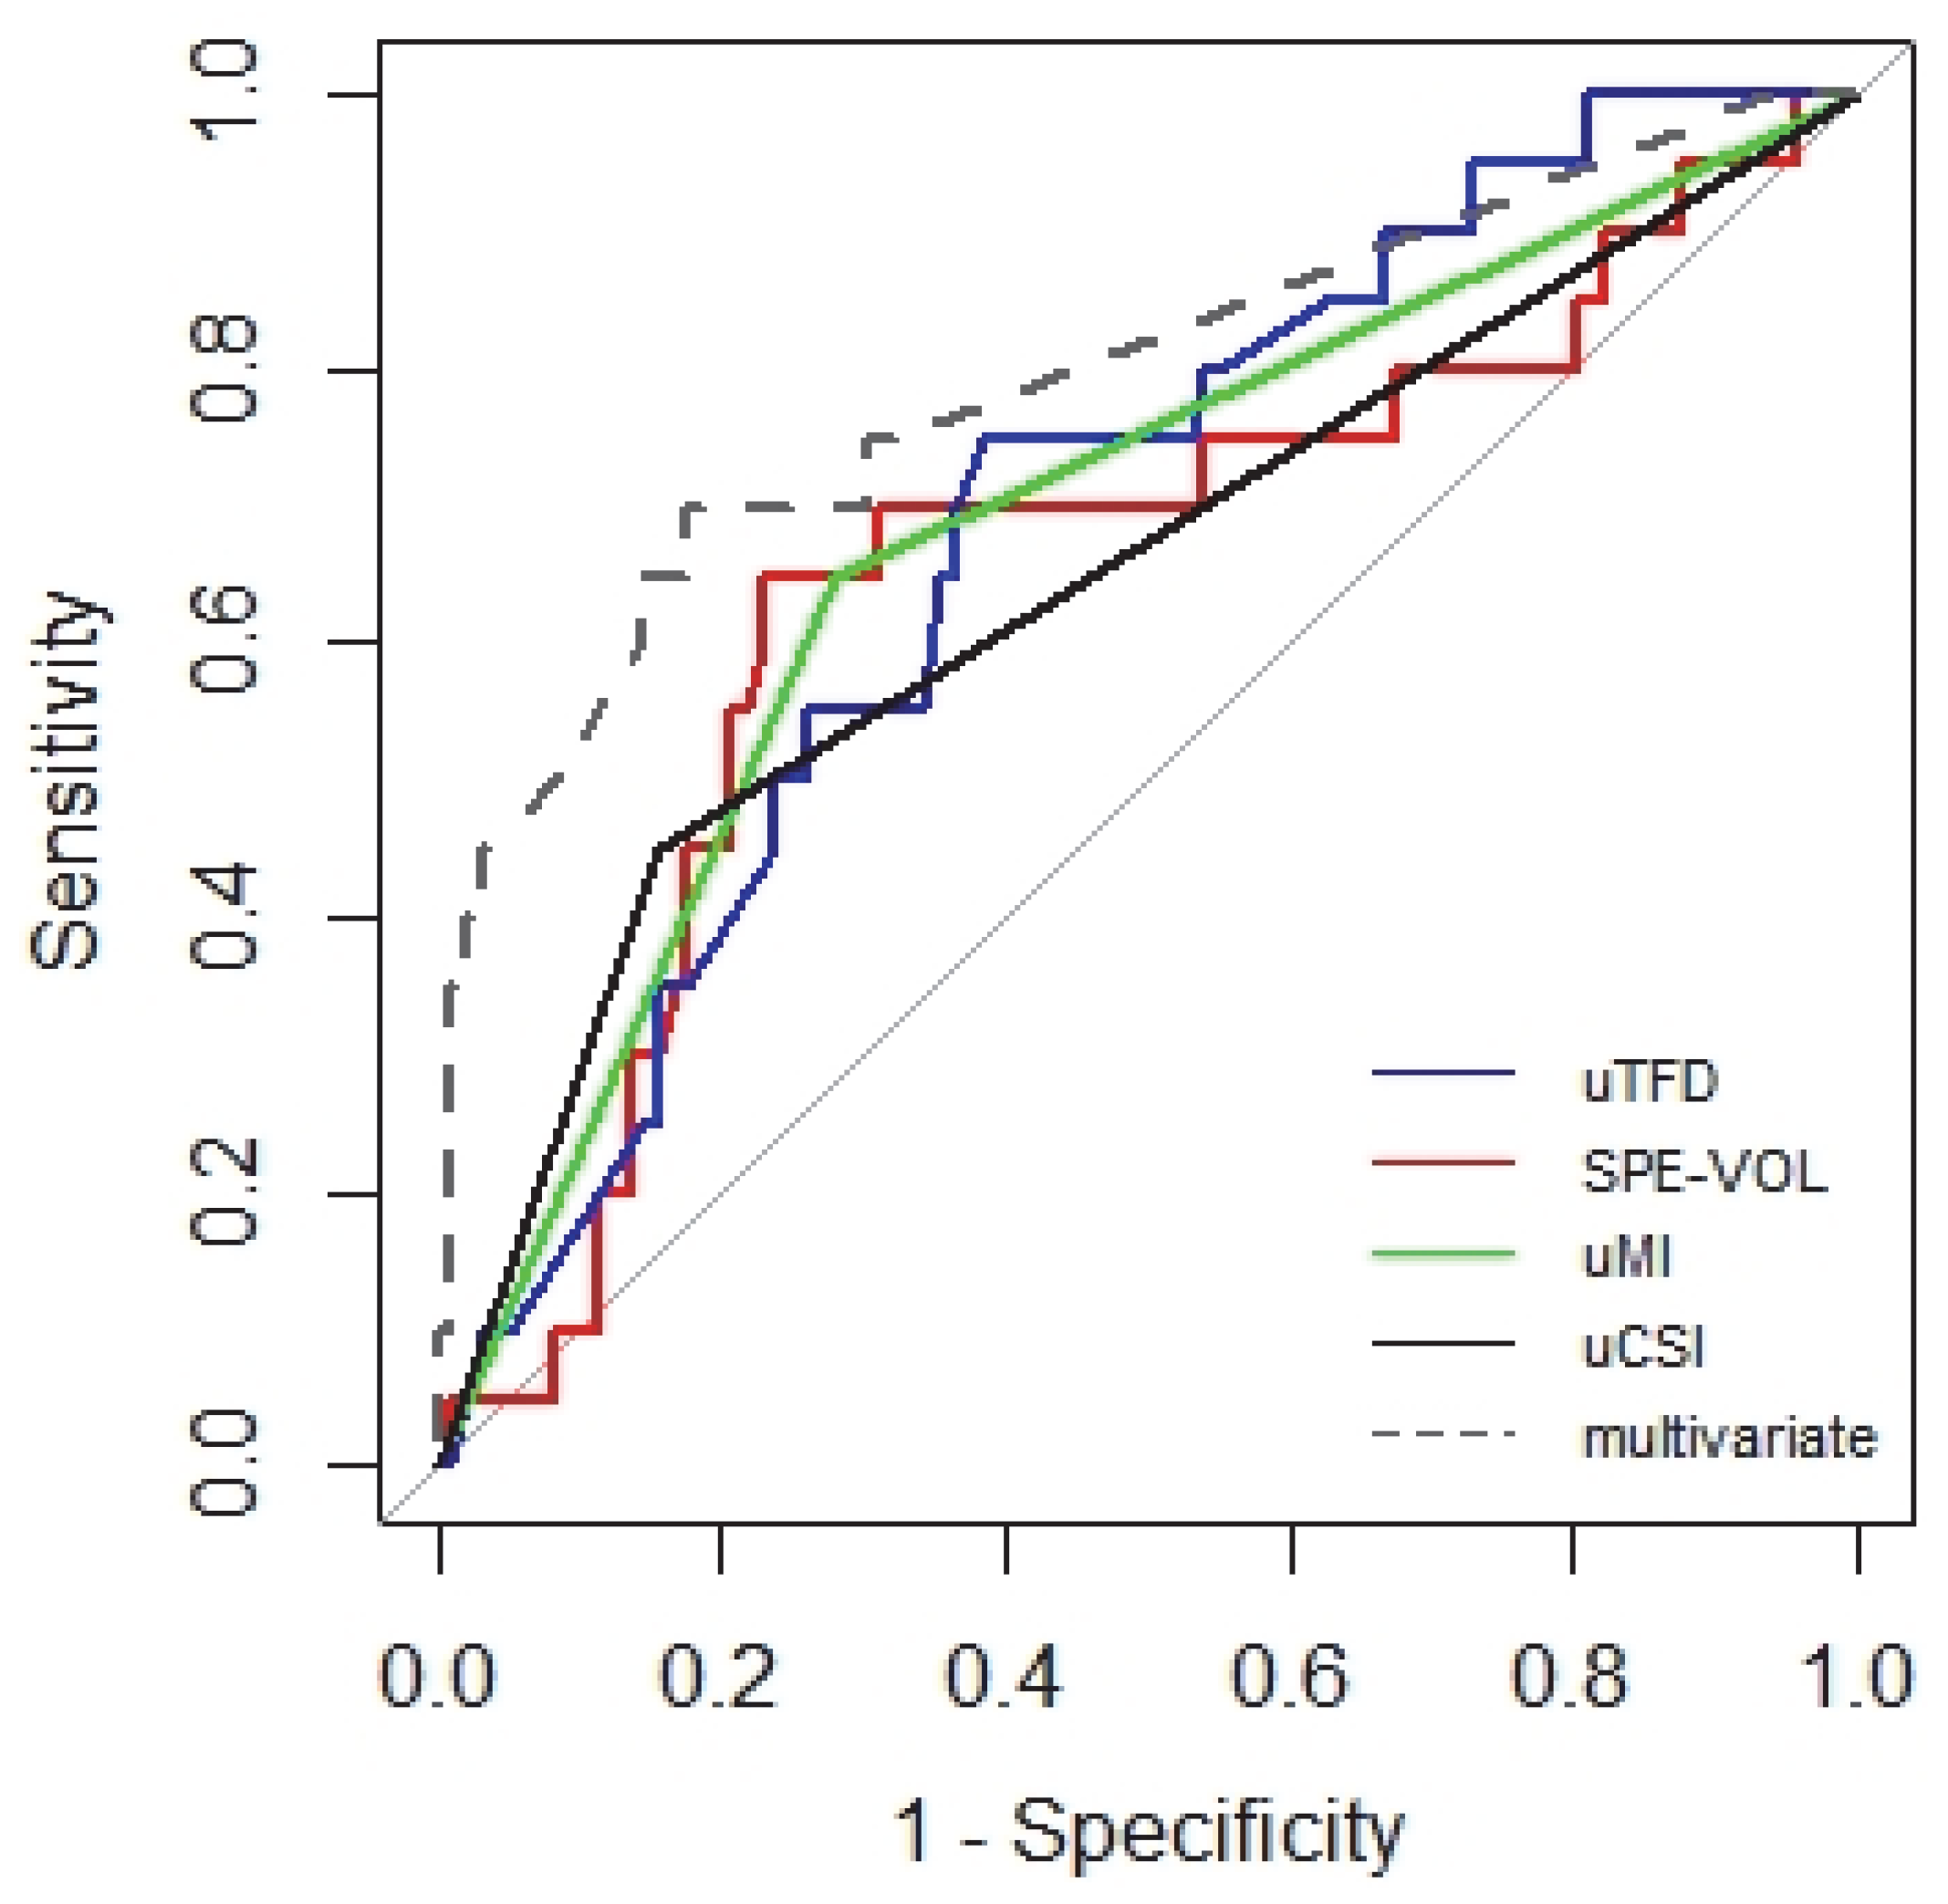

3. Results

4. Discussion

5. Conclusions